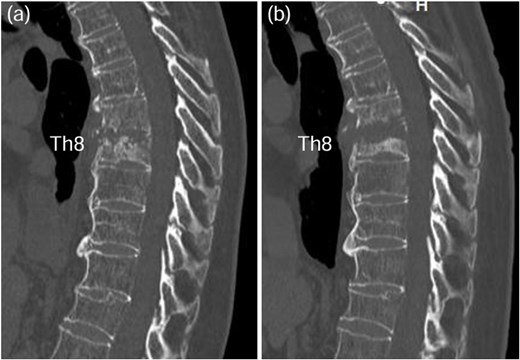

A 75-year-old woman presented with a 1-month history of lower back pain. She had no prior history suggestive of being immunocompromised. No neurological deficits were observed; however, the patient experienced severe back pain, which made it difficult to maintain a seated position. A computed tomography (CT)scan revealed erosion of showed the Th7-Th8 vertebral endplates, with associated diffuse idiopathic skeletal hyperostosis (DISH) (Fig. 1a). Blood tests showed a mild increase in inflammatory markers (C-reactive protein [CRP]: 1.02 mg/dL, white blood cells [WBC]: 6.0 × 103 per μL). Magnetic resonance imaging (MRI) demonstrated signal changes in the Th7-Th8 region (Fig. 2). A biopsy of the Th7-Th8 intervertebral disk confirmed the presence of methicillin-susceptible Staphylococcus aureus (MSSA). She was diagnosed with Th7-Th8 pyogenic spondylitis and initially treated conservatively with antibiotics therapy (cefazolin) and a rigid brace. However, after 4 weeks, her symptoms persisted, and a follow-up CT showed further progression of the destructive changes at the Th7-Th8 endplates (Fig. 1b). Her WBC was 6.4 × 103 per μL, and CRP was 1.19 mg/ dL. Spinal instrumentation surgery was planned, and an assessment of osteoporosis was conducted. The T-scores at the lumbar spine and total hip were −1.4 and −0.9, respectively, and the Hounsfield unit (HU) value at L1 was 79. Posterior PPS fixation was performed from Th5 to Th10 using CAPS at Th5 and Th10, along with the placement of a TMC at Th7-Th8 via a costovertebral approach (Fig. 3). Blood examination results returned to within the normal range at 3 weeks after surgery. Two years after surgery, there was no recurrence of infection and no evidence of screw loosening. The local kyphosis angle was 11° immediately postoperatively and was maintained at 10° at the final follow-up.

CT scan revealed osteolysis of the Th7-Th8 vertebral endplates and DISH upon admission (a). Four weeks later, progression of destructive changes at the Th7-Th8 endplates was observed (b).